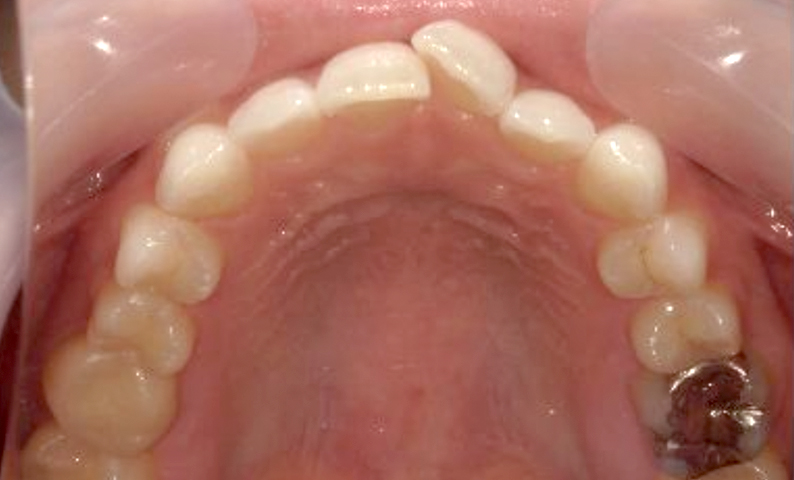

症例_025 上顎だけの部分矯正

治療期間:7ヶ月金額:30万円+税女性前歯のガタガタ上の前歯だけ

| Before | After |